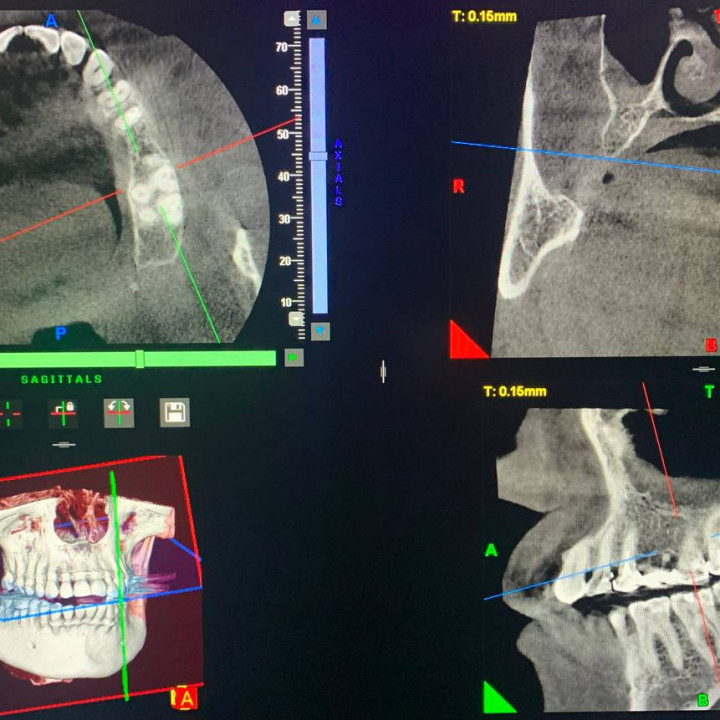

- диагностика при лечении корневых каналов,

- поиск трещин и перфораций корня зуба,

- планирование имплантации зубов,

- исследование по направлению ортодонта,

- диагностика воспаления пазух,

- диагностика заболеваний височно-нижнечелюстного сустава,

При КТ-обследовании трехмерный снимок на экране компьютера возникает в результате объединения большого количества послойных двухмерных снимков в единое целое, что становится возможным благодаря сложному программному обеспечению. Этот метод гораздо информативней традиционной двухмерной плоской рентгенографии зубов и позволяет нашим специалистам максимально эффективно ставить диагноз и проводить лечение.